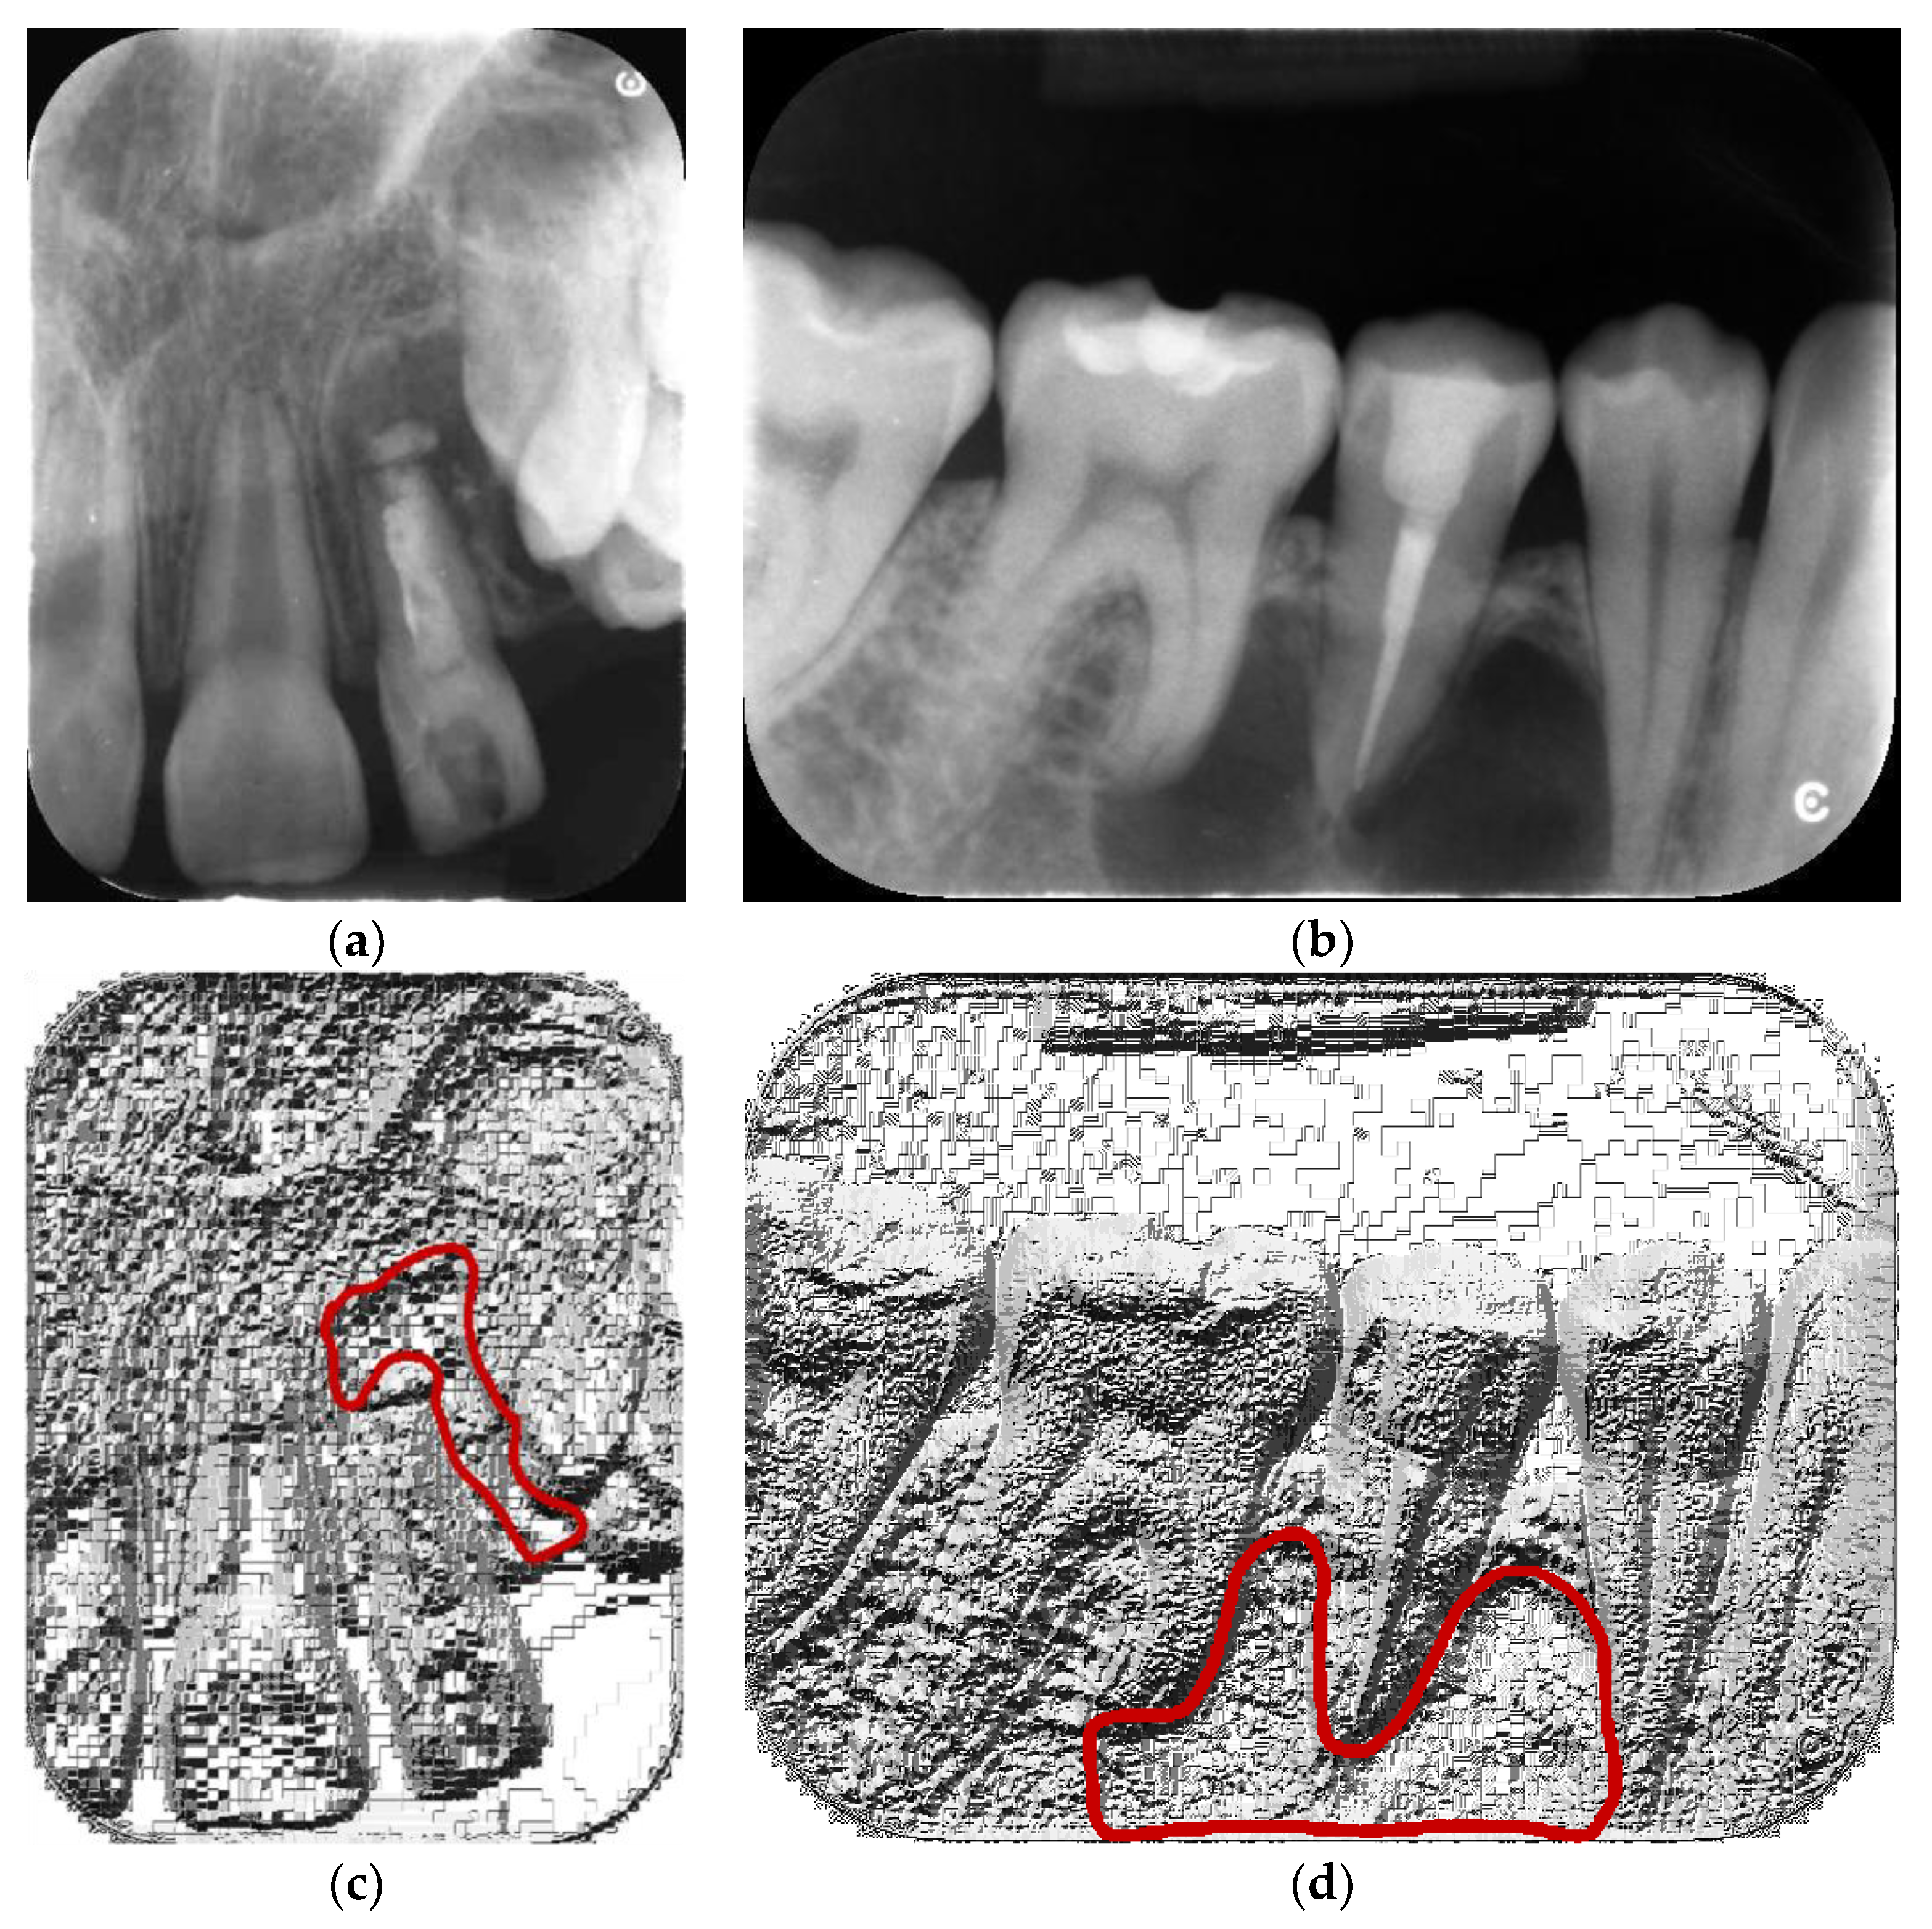

The image database consisted of anonymized, digitalized IR Images from patients who attended the dental clinic presenting lytic lesions from 2015 to 2018. The images were selected from the institutional picture archiving and communication system (PACS), which used lossy JPG without scale preservation as the storage format (Figure 1).

Figure 1.

Example of lossy compression artifacts on local binary pattern (LBP) feature maps (c,d) calculated for analyzed JPG images (a,b). Lesions are depicted with red lines.